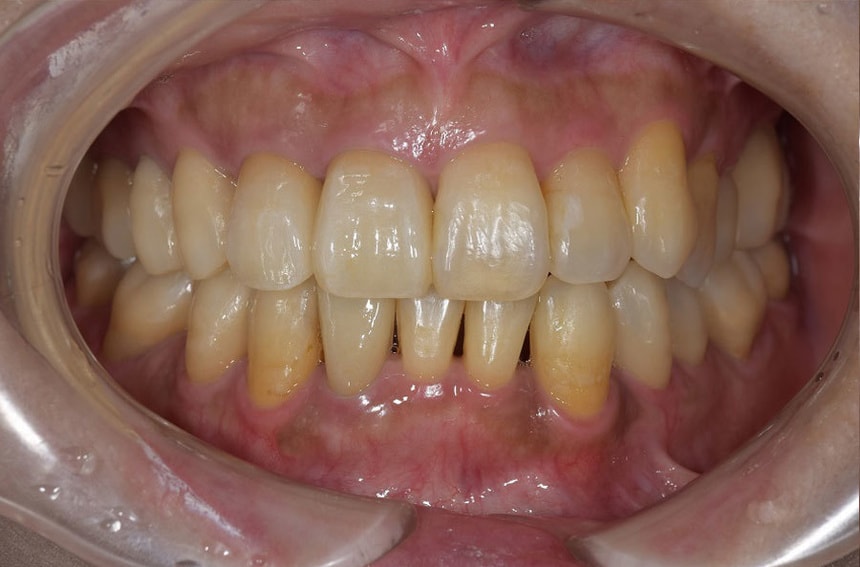

前歯の治療前後

最小限の矯正治療や過去に治療した銀歯の隙間から虫歯になった歯や神経の再治療を行いました。もう少し修正が必要なのですが、部分矯正も含め長い治療になり、とりあえずはお疲れさまでした。

治療は、僕たちは当然ですが、患者さんにも頑張って頂いて初めてうまくいくものかなとも思います。定期的に通院していただいたり、治療が間延びしないことも治療がうまくいく要因の一つのように感じます。

治療が終了して終わりではなく、維持するためこれからメンテナンスが、始まると思っていただければ幸いです。現状が、できるだけ長期に維持できればと考えています。